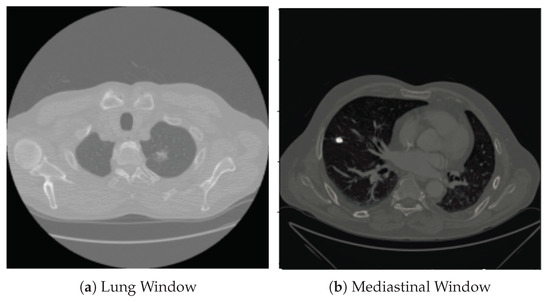

2.2.1. Segmentation in Lung Window

2.2.2. Segmentation in Mediastinal Window